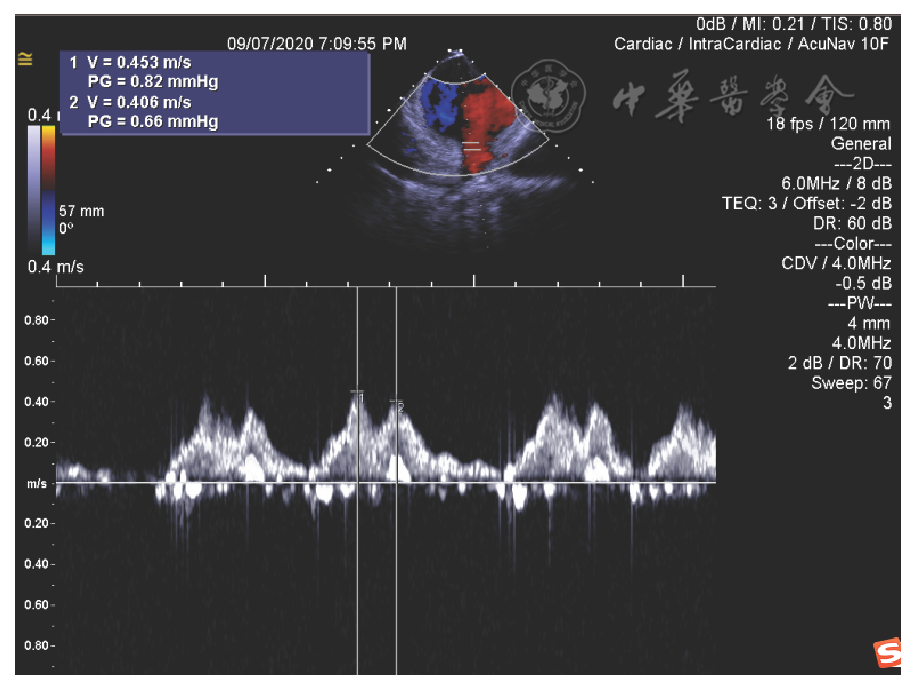

图15 结合血流速度和二维影像,定位肺静脉口,避免消融致其狭窄